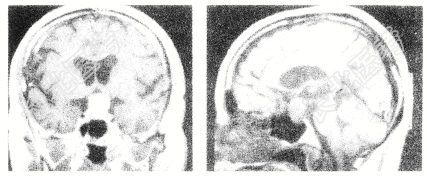

- 单项选择题患者,男性, 32岁。视物模糊,部分视野缺失, 伴有头痛、恶心2个月,MRI检查如下图。患者最可能诊断为( )。

A、蛛网膜囊肿

B、颅咽管瘤

C、表皮样囊肿

D、垂体瘤

E、脑膜瘤